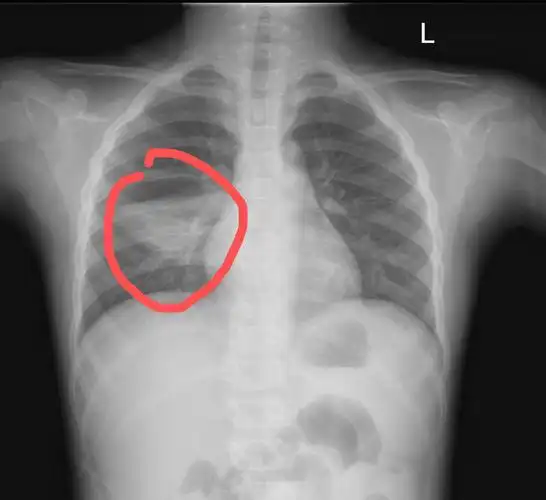

胸片可见两肺弥漫炎性渗出影,因此诊断为小儿支气管肺炎